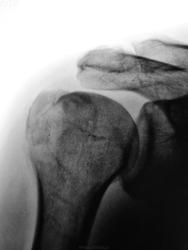

Виновата жена..., упал с дерева...

Данный перелом чреват развитием импиджмент-синдрома

импиджмент-синдром чреват нарушением функции плечевого сустава

нарушение функции плечевого сустава чревато невозможностью более лазить по деревьям